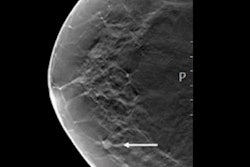

They looked at data from 14,768 Swedish women in the Malmö Breast Tomosynthesis Screening Trial. The average age of the women was 57 years. Of the 136 cancers found, 95 were detected on 2D digital mammography and 41 were detected only on DBT.

A cancer was defined as AI-detected if the cancer lesion was correctly localized and had a score of at least 62, the threshold determined by the software developers. If a score of 62 or higher was reached, the lesion was given the maximum examination risk score of 10.

The highest examination risk score was assigned to 1,493 breast exams, about 10.1% of the total patient cohort. The AI system detected 71 of the digital mammography-detected cancers. Of the cancers that radiologists detected on DBT only, 18 were detected by the AI system, 17 of which were invasive.